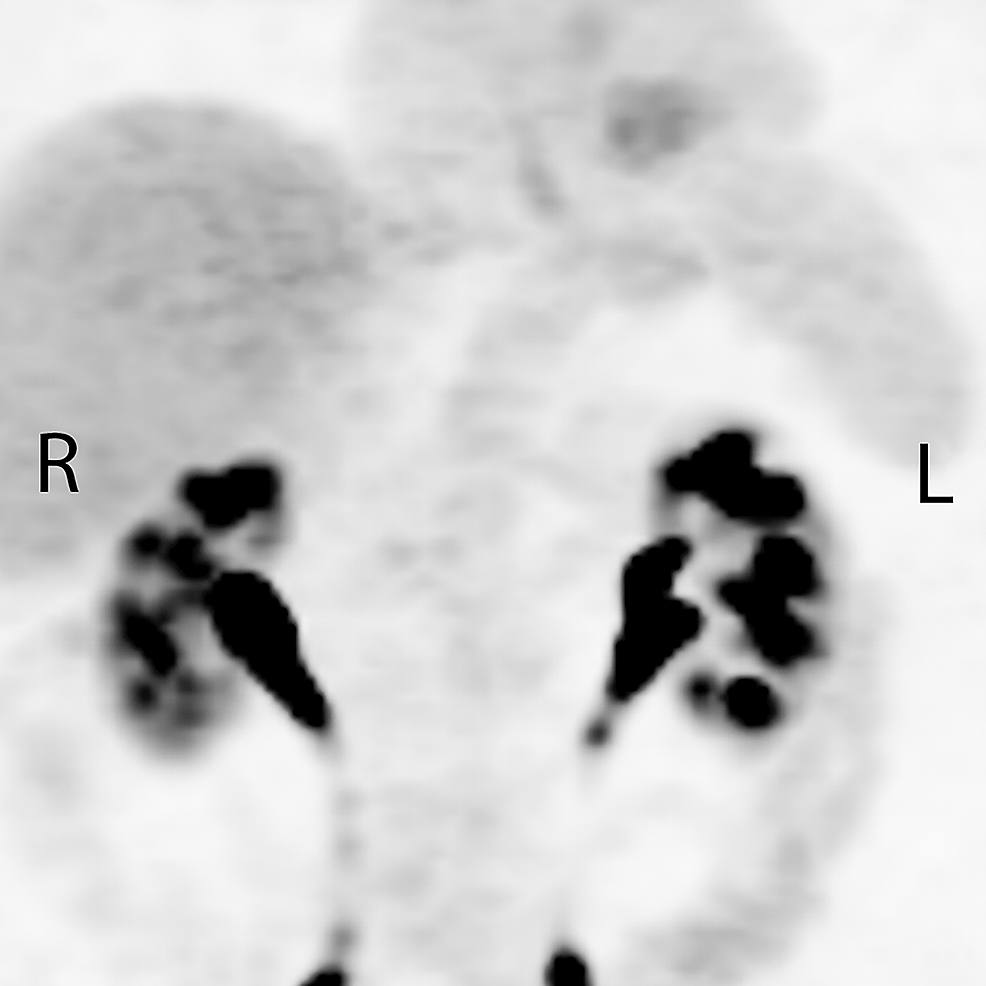

From March 21, 2016 to April 5, 2016, the patient received palliative RT to the symptomatic primary tumor and closest adjacent nodes using a pair of anterior and posterior fields. A total dose of 30 Gray (Gy) was prescribed over 10 daily fractions. As the lymphadenopathy in the lower abdomen was not symptomatic, and would have contributed to increased toxicity, this region was deliberately excluded from the high dose RT volume (Figure 2). Other than very mild odynophagia, the patient had no other RT-related side effects. On the first follow-up visit, one month following treatment completion, he had improved swallowing function and a weight gain of six pounds.

Follow-up computed tomography (CT) scan was obtained on May 24, 2016 to evaluate for the suitability of chemotherapy and to serve as a baseline during systemic therapy. This demonstrated persistent thickening of the lower esophagus, with lymphadenopathy reported to have decreased in size and no significant retroperitoneal adenopathy. When given the option of receiving palliative chemotherapy, the patient declined and chose to continue on observation only. Further CT scans in August and October 2016 showed a complete response in the irradiated primary tumor and nodes, with a stable 10 mm lymph node at the right renal vein.